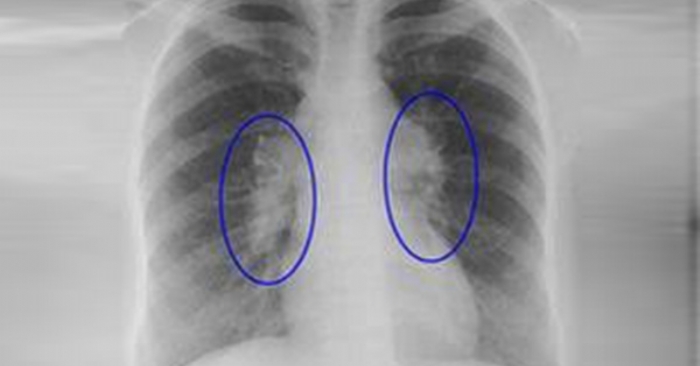

Diaqnoz qoyulması üçün həkimlər bir neçə üsuldan istifadə edir. Əsasən rentgen və ya kompüter tomoqrafiyası ilə ağciyərlər müayinə olunur, qan analizləri aparılır və dəqiq təsdiq üçün biopsiya ilə toxuma nümunəsi götürülür.